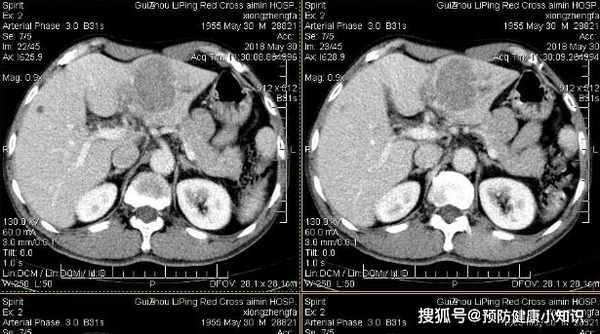

送到醫院後,經過一系列檢查,肝CT竟然發現,肝內有异常占位,確診為肝癌晚期。